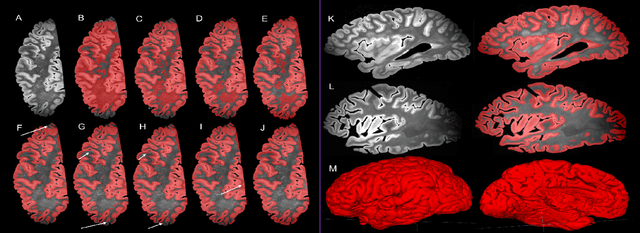

Abstract:Magnetic resonance imaging (MRI) is the standard modality to understand human brain structure and function in vivo (antemortem). Decades of research in human neuroimaging has led to the widespread development of methods and tools to provide automated volume-based segmentations and surface-based parcellations which help localize brain functions to specialized anatomical regions. Recently ex vivo (postmortem) imaging of the brain has opened-up avenues to study brain structure at sub-millimeter ultra high-resolution revealing details not possible to observe with in vivo MRI. Unfortunately, there has been limited methodological development in ex vivo MRI primarily due to lack of datasets and limited centers with such imaging resources. Therefore, in this work, we present one-of-its-kind dataset of 82 ex vivo T2w whole brain hemispheres MRI at 0.3 mm isotropic resolution spanning Alzheimer's disease and related dementias. We adapted and developed a fast and easy-to-use automated surface-based pipeline to parcellate, for the first time, ultra high-resolution ex vivo brain tissue at the native subject space resolution using the Desikan-Killiany-Tourville (DKT) brain atlas. This allows us to perform vertex-wise analysis in the template space and thereby link morphometry measures with pathology measurements derived from histology. We will open-source our dataset docker container, Jupyter notebooks for ready-to-use out-of-the-box set of tools and command line options to advance ex vivo MRI clinical brain imaging research on the project webpage.

Abstract:Ex vivo MRI of the brain provides remarkable advantages over in vivo MRI for visualizing and characterizing detailed neuroanatomy, and helps to link microscale histology studies with morphometric measurements. However, automated segmentation methods for brain mapping in ex vivo MRI are not well developed, primarily due to limited availability of labeled datasets, and heterogeneity in scanner hardware and acquisition protocols. In this work, we present a high resolution dataset of 37 ex vivo post-mortem human brain tissue specimens scanned on a 7T whole-body MRI scanner. We developed a deep learning pipeline to segment the cortical mantle by benchmarking the performance of nine deep neural architectures. We then segment the four subcortical structures: caudate, putamen, globus pallidus, and thalamus; white matter hyperintensities, and the normal appearing white matter. We show excellent generalizing capabilities across whole brain hemispheres in different specimens, and also on unseen images acquired at different magnetic field strengths and different imaging sequence. We then compute volumetric and localized cortical thickness measurements across key regions, and link them with semi-quantitative neuropathological ratings. Our code, containerized executables, and the processed datasets are publicly available at: https://github.com/Pulkit-Khandelwal/upenn-picsl-brain-ex-vivo.

Abstract:When developing tools for automated cortical segmentation, the ability to produce topologically correct segmentations is important in order to compute geometrically valid morphometry measures. In practice, accurate cortical segmentation is challenged by image artifacts and the highly convoluted anatomy of the cortex itself. To address this, we propose a novel deep learning-based cortical segmentation method in which prior knowledge about the geometry of the cortex is incorporated into the network during the training process. We design a loss function which uses the theory of Laplace's equation applied to the cortex to locally penalize unresolved boundaries between tightly folded sulci. Using an ex vivo MRI dataset of human medial temporal lobe specimens, we demonstrate that our approach outperforms baseline segmentation networks, both quantitatively and qualitatively.

Abstract:Ex vivo MRI of the brain provides remarkable advantages over in vivo MRI for visualizing and characterizing detailed neuroanatomy. However, automated cortical segmentation methods in ex vivo MRI are not well developed, primarily due to limited availability of labeled datasets, and heterogeneity in scanner hardware and acquisition protocols. In this work, we present a high resolution 7 Tesla dataset of 32 ex vivo human brain specimens. We benchmark the cortical mantle segmentation performance of nine neural network architectures, trained and evaluated using manually-segmented 3D patches sampled from specific cortical regions, and show excellent generalizing capabilities across whole brain hemispheres in different specimens, and also on unseen images acquired at different magnetic field strength and imaging sequences. Finally, we provide cortical thickness measurements across key regions in 3D ex vivo human brain images. Our code and processed datasets are publicly available at https://github.com/Pulkit-Khandelwal/picsl-ex-vivo-segmentation.